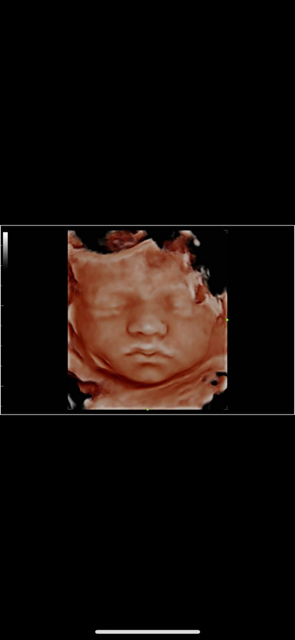

The birth of a new baby is an exciting time for parents, family and friends! At Bonding Moments, we offer a warm family atmosphere that offers Elective 2D/3D/4D and HD prenatal ultrasounds. We use state of the art ultrasound technology that allows our trained technicians to bring your baby to life before your very eyes on an 86 in flat screen TV surrounded by up to 12 of your guests. The realistic images will provide a bonding experience between mommy, daddy, family and friends. See baby yawn, hiccup, smile and kick all in real-time. So, let’s take a journey together and peek inside your baby’s world!

A prenatal ultrasound uses a transducer to deliver high frequency sound waves. Echoes of the sound waves are recorded and transformed into pictures. A gel is applied to the belly and transducer before the scan which helps conduct the sound waves. 2D and 3D are still images .4D adds motion and dimension so it looks like a video and HD adds more realism.